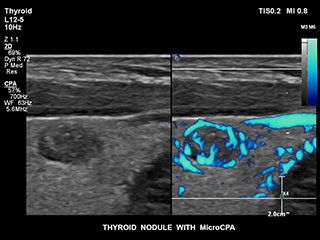

Bisher war die Erfassung von Flussdaten bei kleinen Gefäßstrukturen mit niedriger Flussrate schwierig. Die neue EPIQ Funktion MicroCPA bietet eine schnelle und einfache Darstellung von Mikrozirkulation mit niedriger Geschwindigkeit und ermöglicht eine hohe Diagnosesicherheit bei der Beurteilung der Organperfusion oder von kleinen Gefäßbetten.